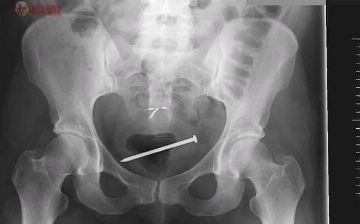

Женщина поместила себе в матку гвоздь, чтобы ее не изнасиловали